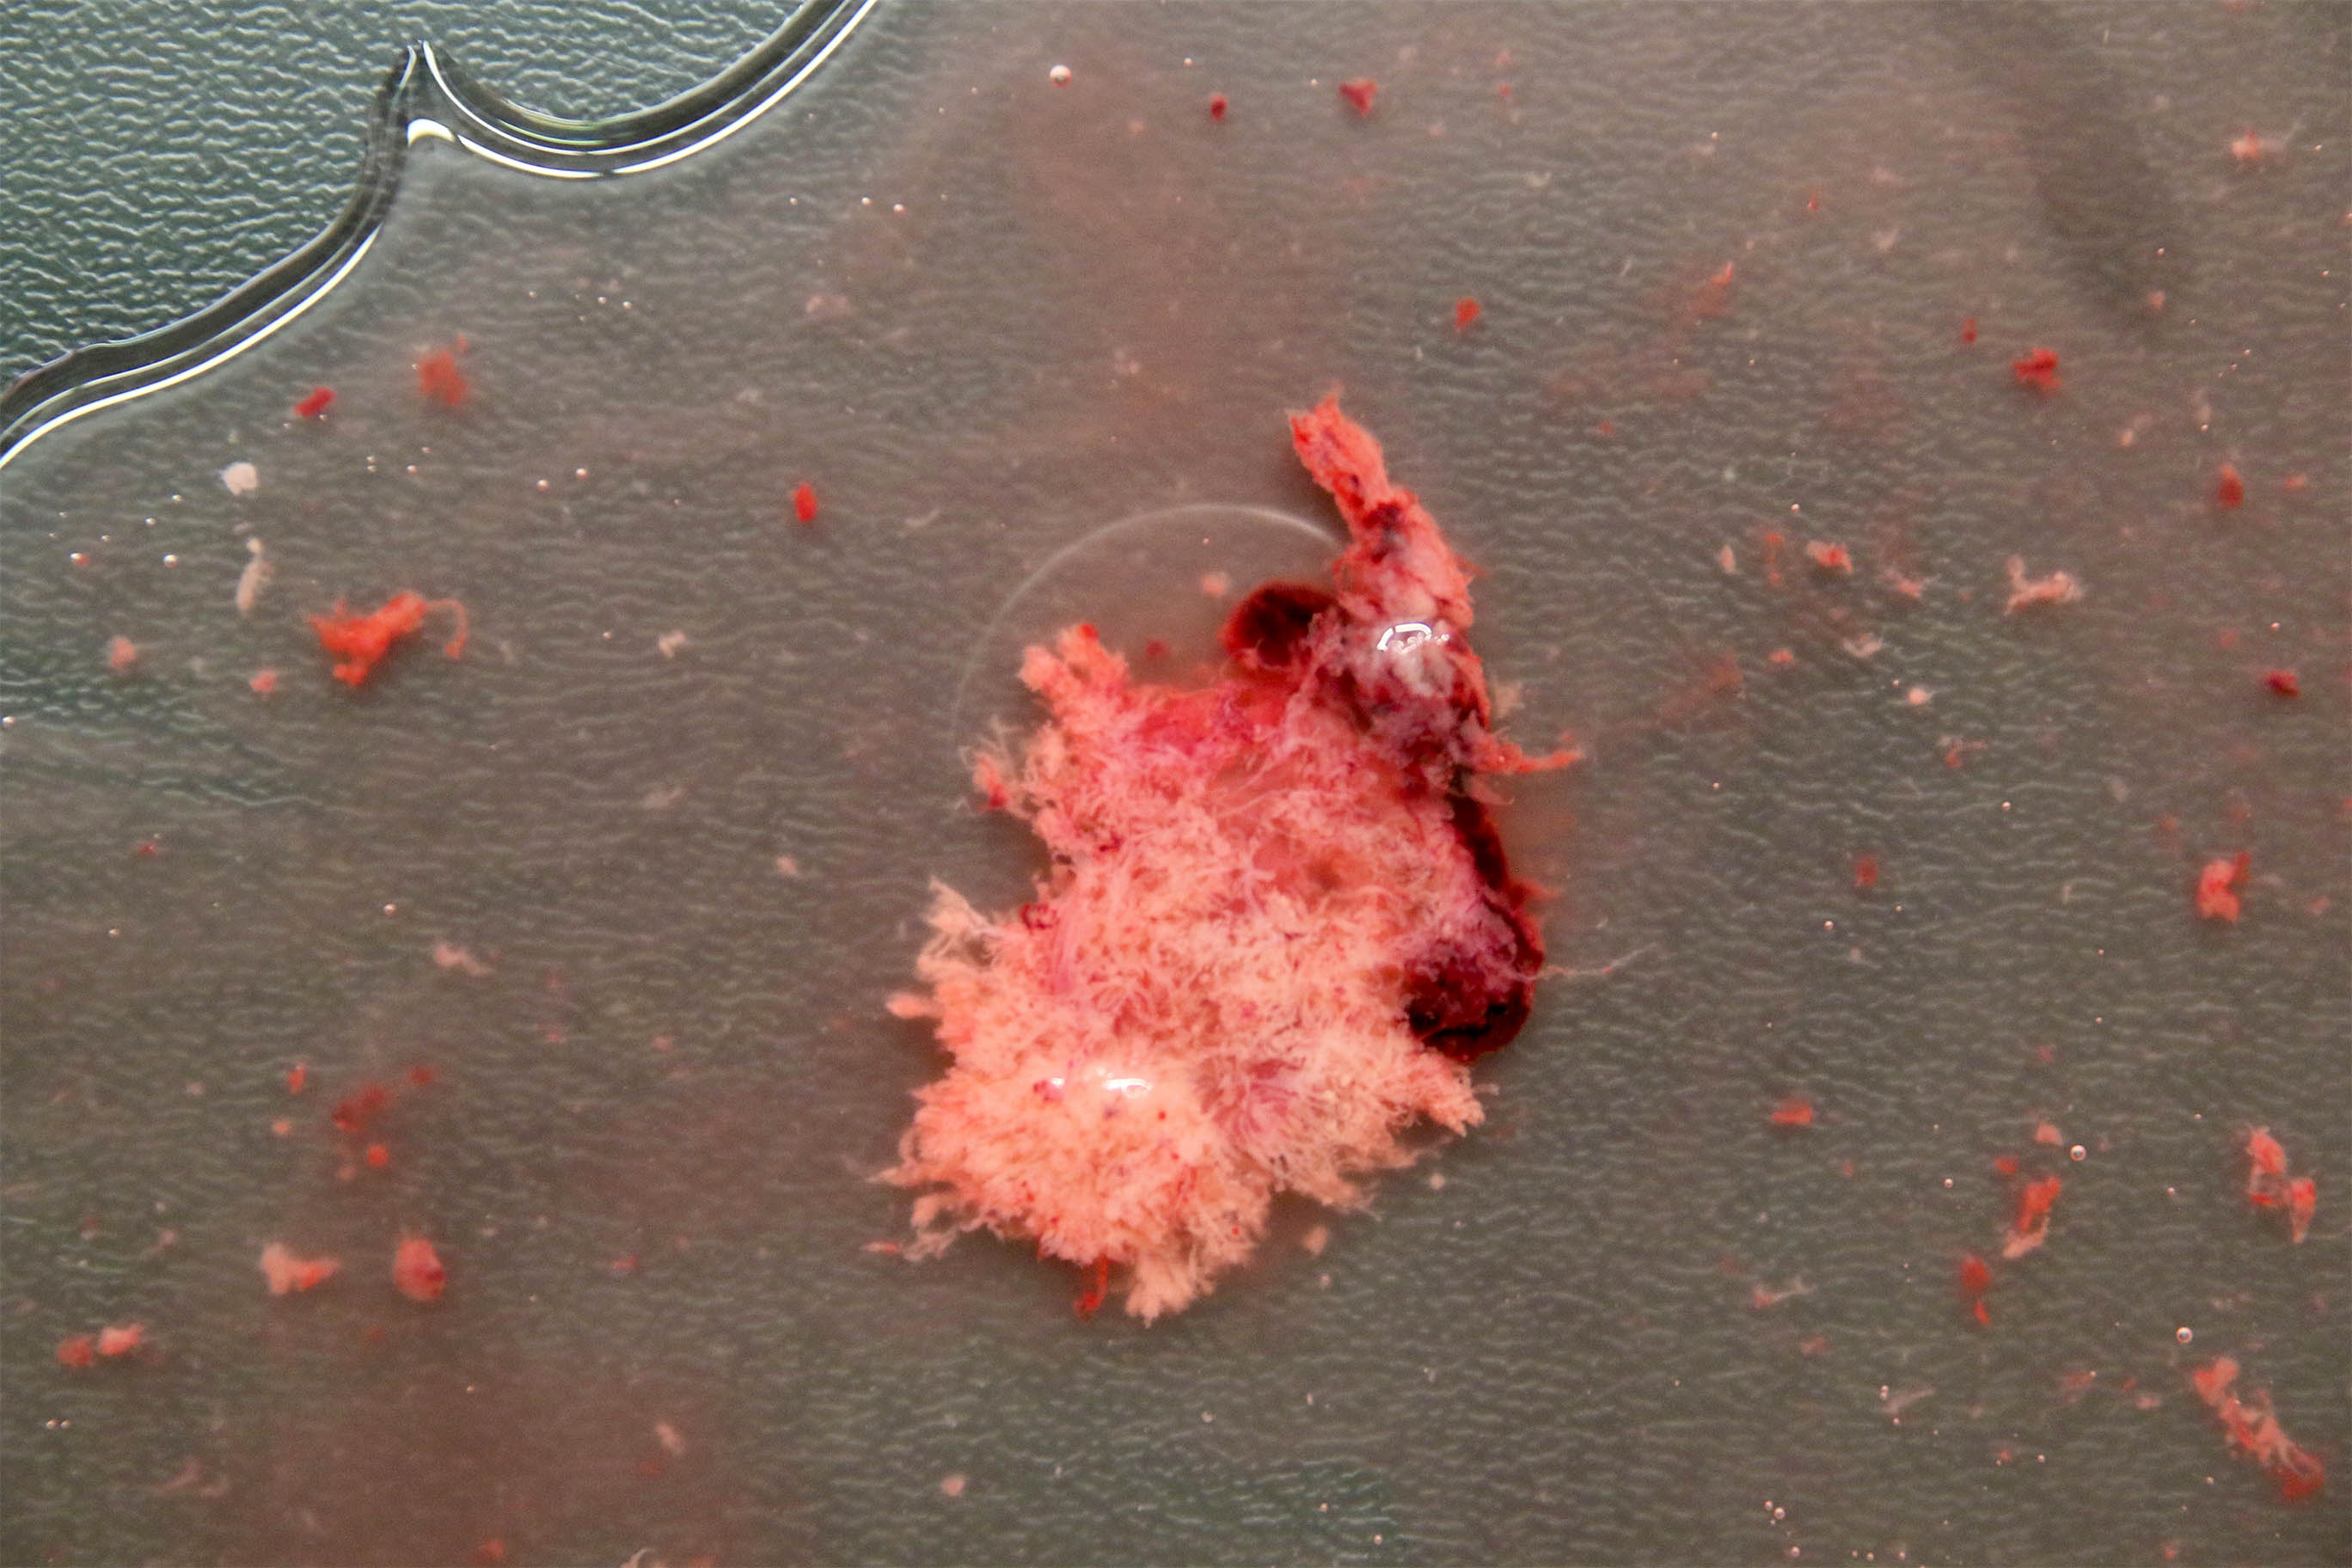

Gross description

- Specimen often consists of fragments of placental tissue (chorionic villi, membranes / gestational sac that may be intact or disrupted and decidua)

- Despite identification of embryo or fetus on ultrasound, an embryo is often not identified / recognized in surgical specimens (J Clin Pathol 1981;34:819)

Gross images